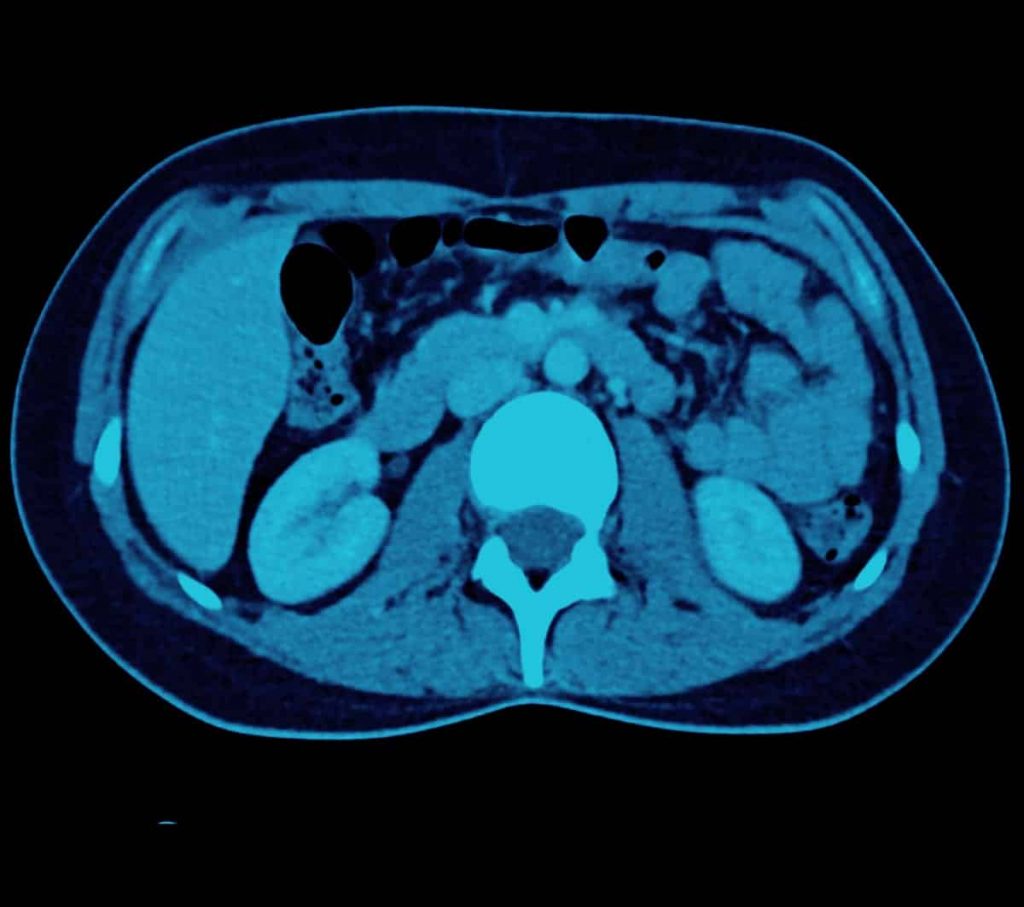

A CT scanner uses an X-ray beam that revolves around a patient to produce a cross sectional-image known as a ‘slice’. Modern CT scanners use multi-slice technology, which means that many fine slices may be performed of the patient as they enter the CT scanner in a single rotation, with the processing of the data resulting in reconstruction of the image from any angle. This means that 3-D images may be produced and assist in the formulation of a diagnosis. The current CT scanner used at Melbourne Radiology Clinic utilises an ultra low radiation dose to acquire diagnostic images, in some cases (particularly in the limbs), lower than a conventional digital X-ray!

Computed Tomography (CT) is of particular use in the diagnosis of chest, abdominal and pelvic disorders, including the bowel and lungs, as well as in the production of images of arteries (known as an angiogram).

Imperial Imaging and Intervention Centre has ithe latest generation ultra-low dose CT scanner that delivers a significantly lower dose whilst at the same time maintaining image quality. This has particular applications in musculoskeletal and orthopaedic imaging, as the dose received in imaging small peripheral joints is comparable, if not lower, than digital X-ray. Imaging of prosthetic joints and other metallic surgical hardware is markedly improved, as well as significant reductions in dose during interventional procedures.